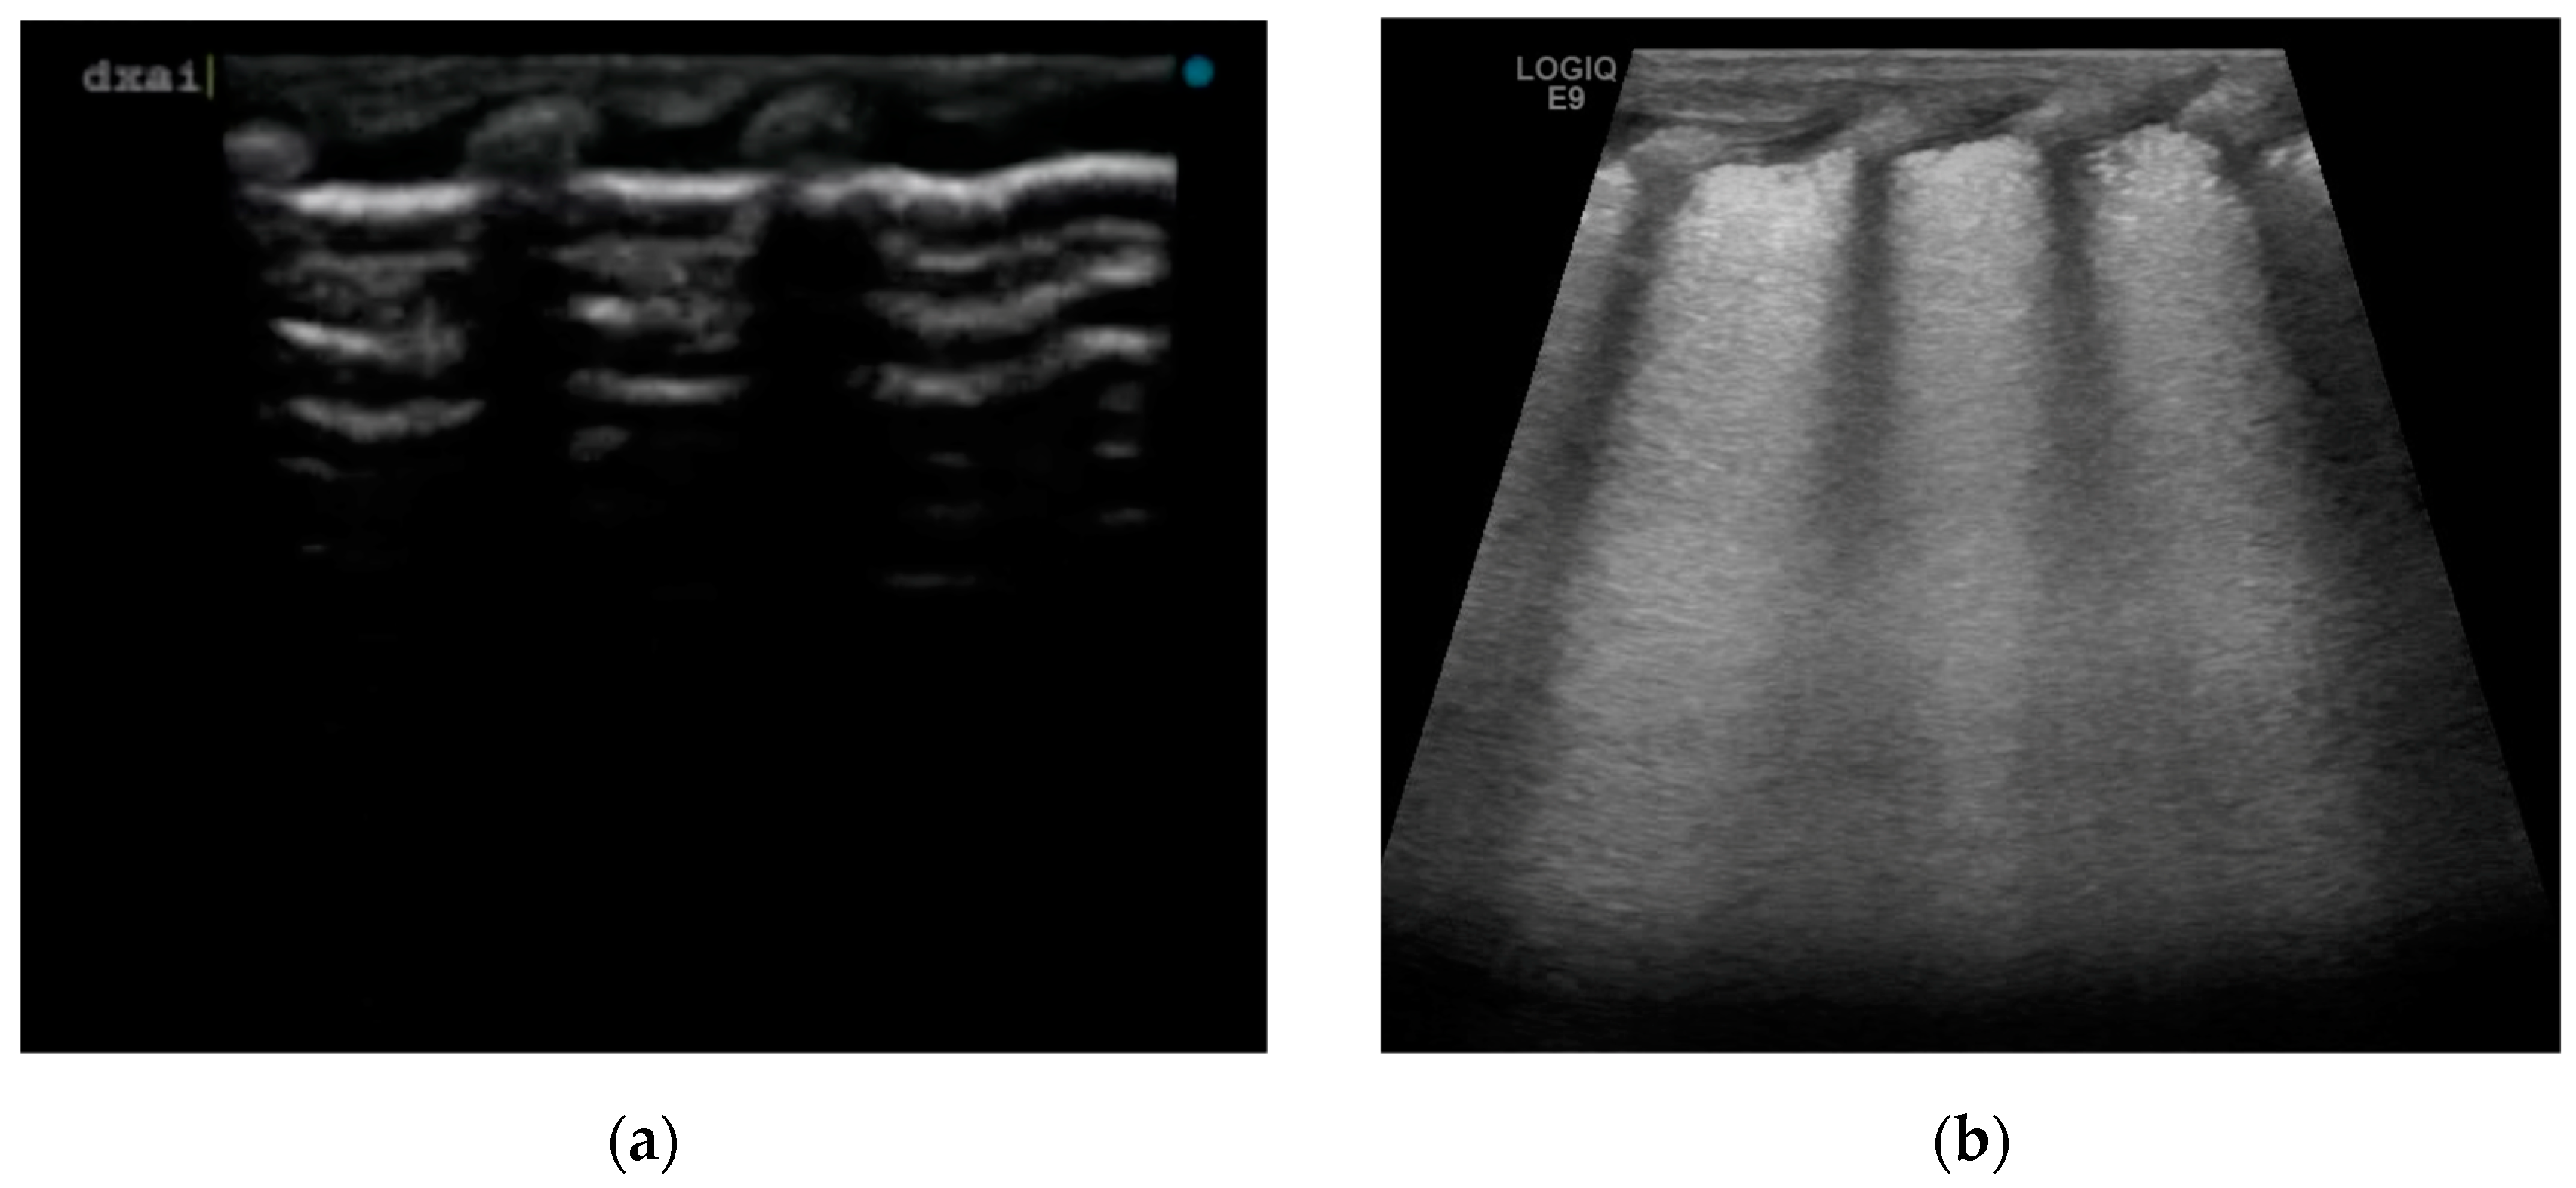

We have described four cases of respiratory distress syndrome in babies born at term or near term from mothers with a diagnosis of ICP during pregnancy, treated with surfactant administration and with a rapid resolution of the respiratory distress symptoms, based on a supposed causative role of BAs in surfactant dysfunction. The diagnosis of ICP was made in the second trimester of pregnancy for two of the four cases, and at 37 weeks of GA in patient 4. All the women were Caucasian. In all patients, we observed early onset of signs and symptoms of respiratory distress after birth, with variable severity. The neonates required non-invasive support with nasal cannula continuous positive airway pressure (CPAP) at the admission in NICU. The lung ultrasounds performed in the first six hours of life, showed the same features for all patients, with a homogeneous alveolar–interstitial syndrome characterized by a diffuse coalescing B-line pattern (white lung), with pleural thickening with some interruption spots and the disappearance of A-line (Figure 1b). None of them had subpleural consolidation. LU scores were predictive of surfactant administration in three of the four cases.

In our center, we perform a lung ultrasound on all infants with respiratory distress syndrome by internal protocol. In these cases, we found a lung ultrasound pattern characterized by a “white lung” and thickening or interruptions of pleural line, that was similar to the pattern usually described for the RDS [10,24].

Figure 1. Lung ultrasound images: (a) normal lung, with A-line pattern; (b) diffuse coalescing B-line pattern (white lung), with pleural thickening with some interruption spots and the disappearance of A-line.